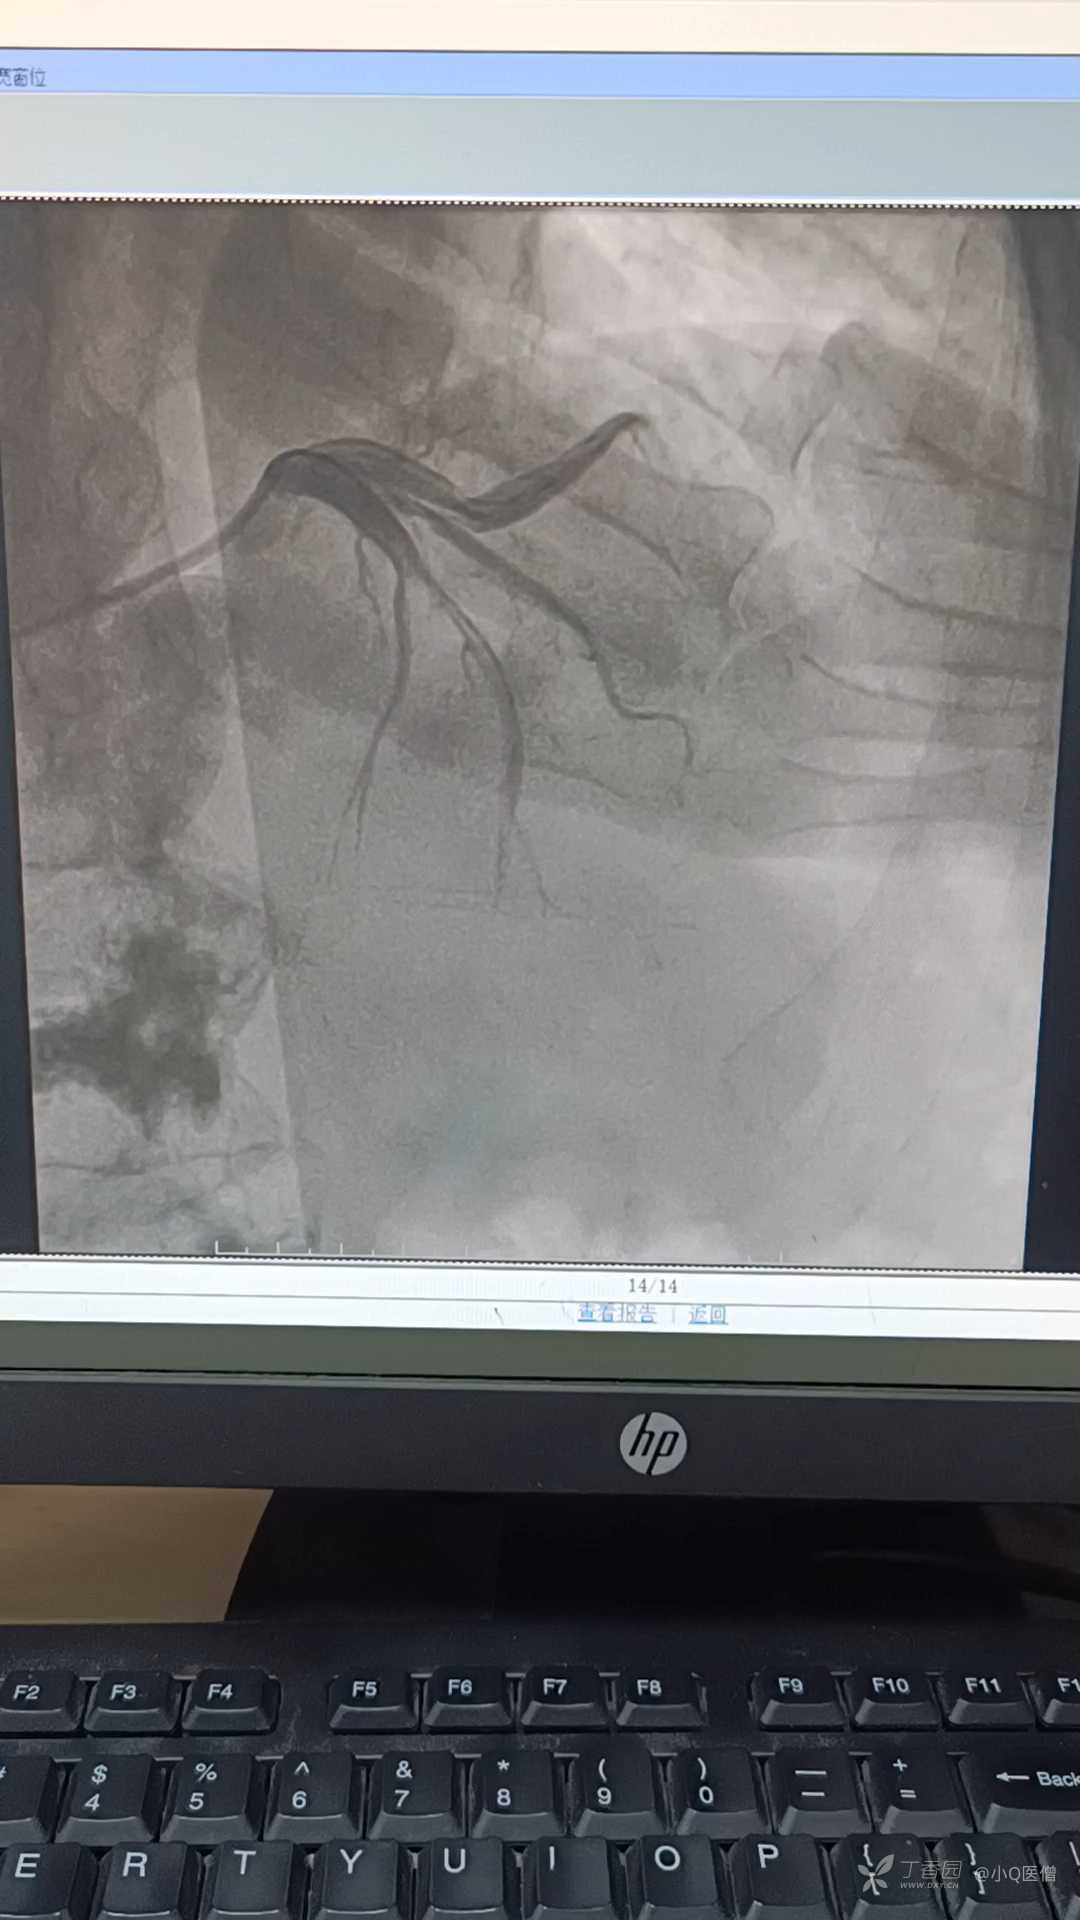

入院第七日,根据患者病情,建议行冠脉造影检查,评估血管情况,家属表示同意,造影结果如下:

LAD近段及D1开口严重狭窄,因考虑ICD及起搏器治疗的可能性未给予双抗,故未做进一步处理。